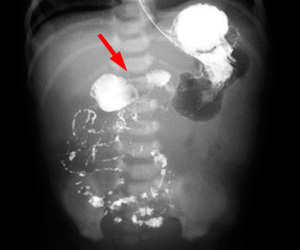

| Cecum is in an abnormal location in the mid pelvis. | The duodenal-jejunal junction is to the right of the spine, and most of the small bowel is on the right side of the abdomen. |

| This shows Ladd Bands resulting in a distended stomach with a small amount of distal gas. | |